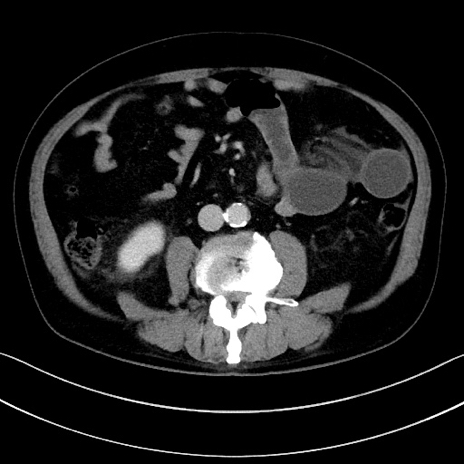

症例

冠状断像